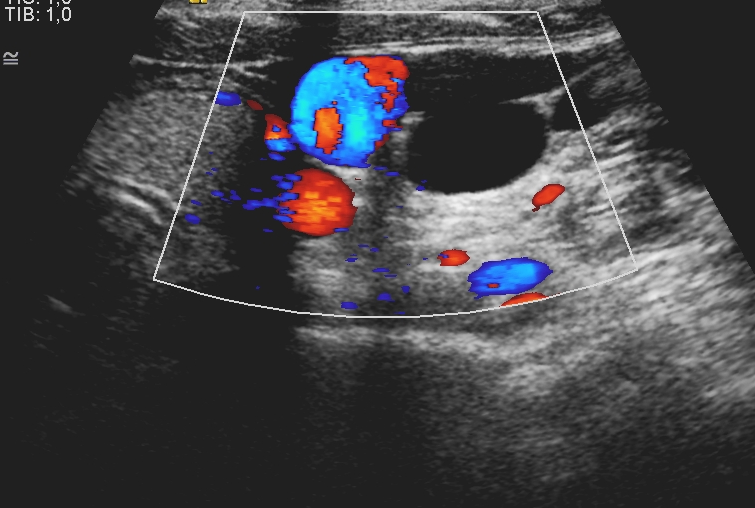

4. image: Young male patient with a left supraclavicular lump. Upper panel: complex cystic mass with sepatations; normal flow in the neighbouring vessels. Lower panel: T2W, postcontrast T1W, fat-saturation T1W MRI suggest cystic lymphangioma (Asklepios Klinik Altona, Hamburg)